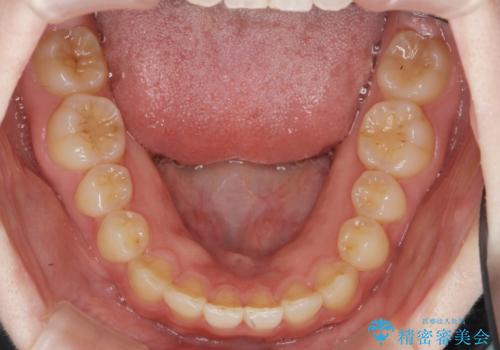

マウスピース矯正では改善の難しい前歯のねじれを前歯の部分ワイヤー矯正で改善したのち、インビザライン矯正を行い歯列を整えます。

インビザラインを行う前に前歯の部分矯正を行ったことで、しっかりとねじれが取れ整った歯列へと仕上げることが出来ました。